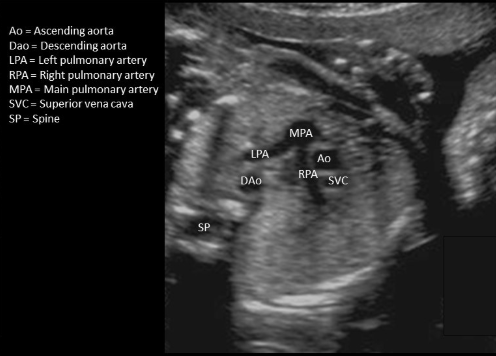

where is superior vena cava

type “next to ascend AO w/o branches”

next to ascend AO w/o branches

where is ascending AO - not seen in this image

type “seen in LVOT tract + aortic arch view”

this is descending AO

seen in LVOT tract + aortic arch view

where is ductus arteriosus

type “MPA-DA-DAo”

MPA-DA-DAo

where is the AO in this 3 vessel view - which dot is it

a) top

b) middle

c) bottom

what is letter A

a) descending AO

b) ascending AO

c) main pulmonary artery

d) aortic arch

where is the ascending AO

type “MPA-AO-SVC”

MPA-AO-SVC

type “between main pulmonary artery + right atrium”

descending ao is posterior to ductus arteriosus

between main pulmonary artery + right atrium

where is the left pulmonary artery

“branch closer to descending AO"

branch closer to descending AO